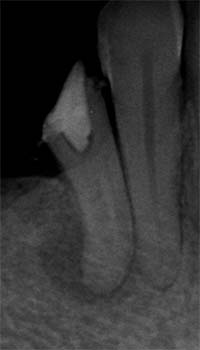

側枝の取り残し

![]() |

| 術前 | 当院にて根充 |

そこで当院では、「成功率に直結する全7工程を、例外なく毎回行う」という標準化(Standardization)を徹底しています。

この標準化こそ、他院で治らなかった歯でも改善する可能性が高い理由です。以下では、当院の全工程を詳しくご紹介します。